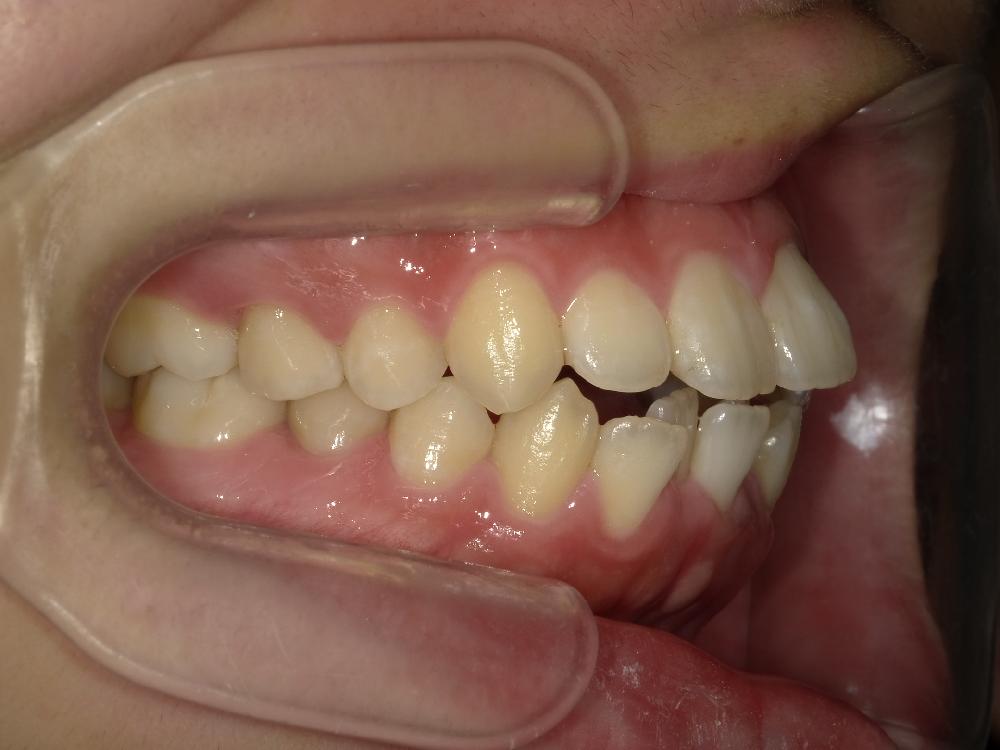

治療前左側

治療前右側